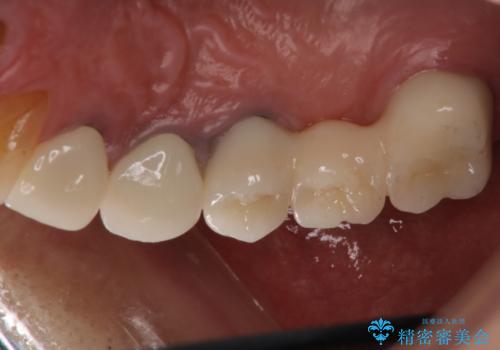

歯肉からの出血 適合の悪い銀歯をオールセラミックのブリッジにやり替え

- 右上奥歯の歯肉から出血があり異和感をおぼえ来院された患者様です。

以前の被せ物を除去し、仮歯に変えてすぐに異和感がとれました。

歯周治療を行い、歯肉が引き締まってから補綴治療しました。